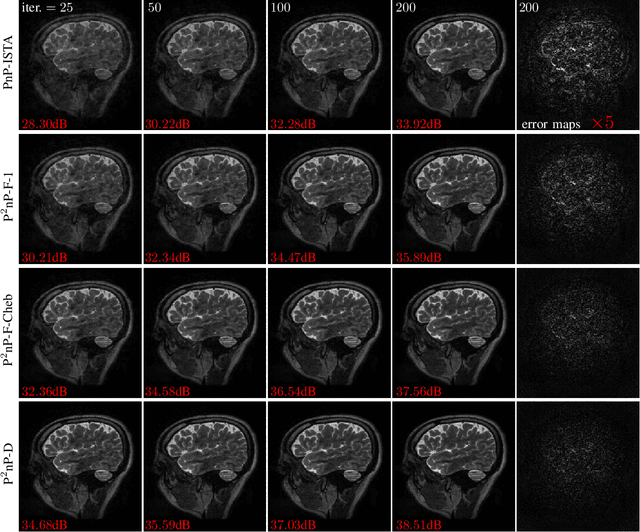

Model-based methods play a key role in the reconstruction of compressed sensing (CS) MRI. Finding an effective prior to describe the statistical distribution of the image family of interest is crucial for model-based methods. Plug-and-play (PnP) is a general framework that uses denoising algorithms as the prior or regularizer. Recent work showed that PnP methods with denoisers based on pretrained convolutional neural networks outperform other classical regularizers in CS MRI reconstruction. However, the numerical solvers for PnP can be slow for CS MRI reconstruction. This paper proposes a preconditioned PnP (P^2nP) method to accelerate the convergence speed. Moreover, we provide proofs of the fixed-point convergence of the P^2nP iterates. Numerical experiments on CS MRI reconstruction with non-Cartesian sampling trajectories illustrate the effectiveness and efficiency of the P^2nP approach.